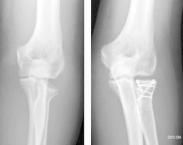

橈骨頭的頭、頸部骨折約占肘部損傷的6%,屬于關節內骨折。由于橈骨頭、頸骨折的固定需要特殊的技術和方法才能達到穩定,這在臨床上不易做到,因此,目前橈骨頭、頸骨折的治療和處理方法仍存在很多爭議。